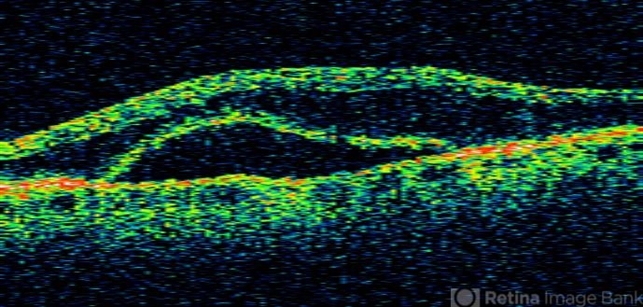

- macular detachment, myeloma

Optical coherence tomography system

stratus - Description

- 84 year-old white male with blurred vision over 2 months. Has incidental BVO.